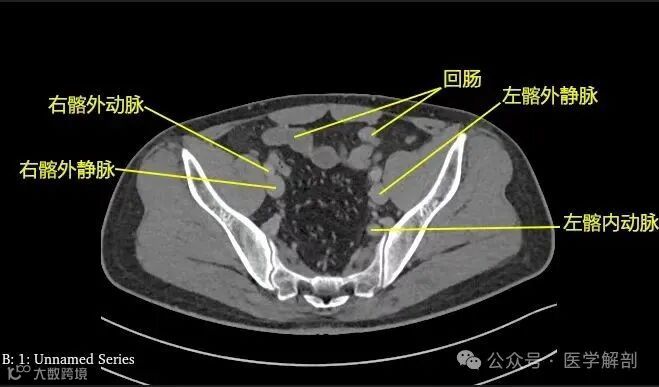

第三骶椎中部

第三骶椎平面标注